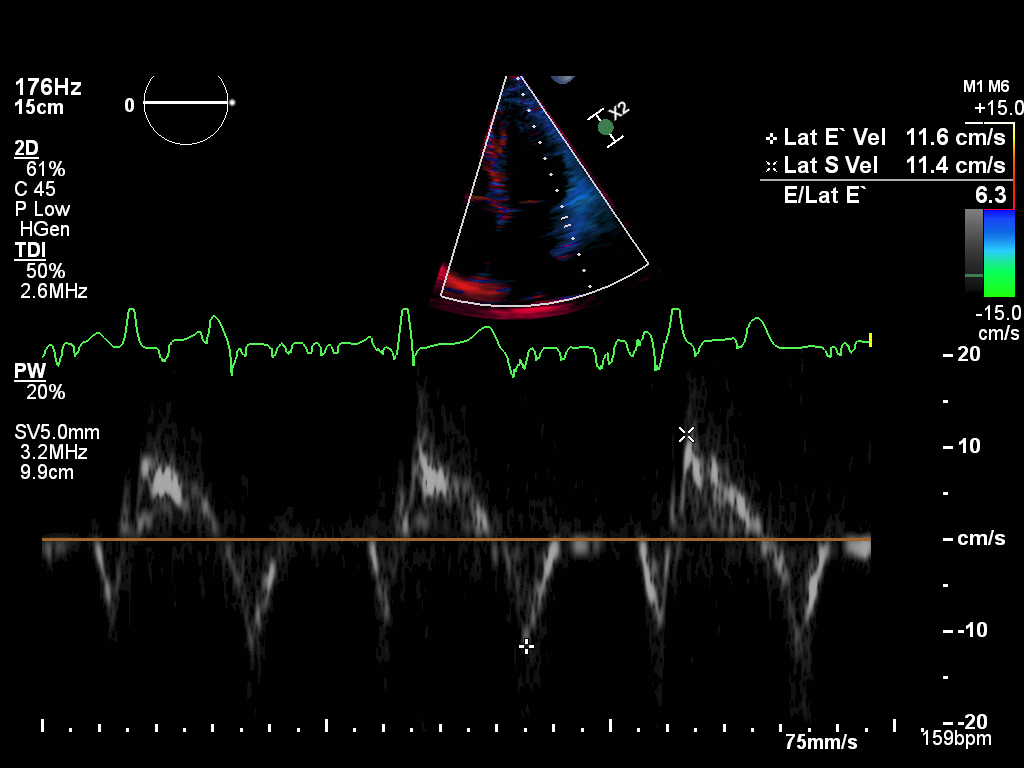

doppler-tissue-lateral doppler-tissue-lateral Tissue Doppler of the LV lateral wall